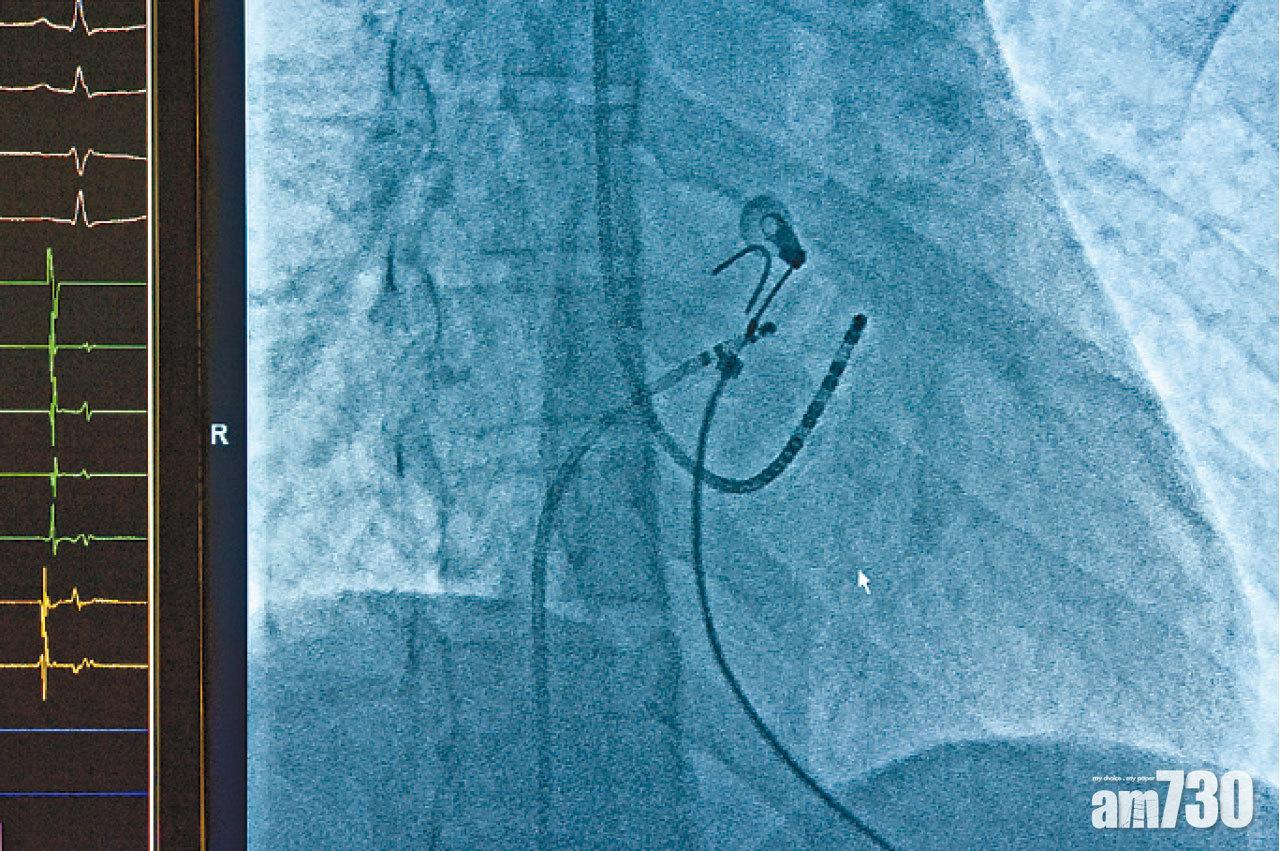

導管消融術可找出心臟不正常跳動的部分,並以射頻控制引致房顫的電流。

如要更有效改善心房顫動,馮永康建議患者接受「導管消融術」,「這類手術透過導管,找出心臟不正常跳動的部分,並以射頻控制引致房顫的電流,近八成患者接受相關手術後,病情得到大幅改善。」他強調,這類手術的風險不高,但如患者年紀大,亦有不同風險因素,則應繼續以薄血藥治療。